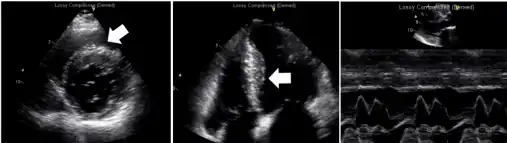

-

Echocardiogram exam shows left atrial enlargement (asymmetrical septal hypertrophy without left ventricle (LV) outflow tract obstruction, restrictive filling pattern, normal LV systolic function)[6] -